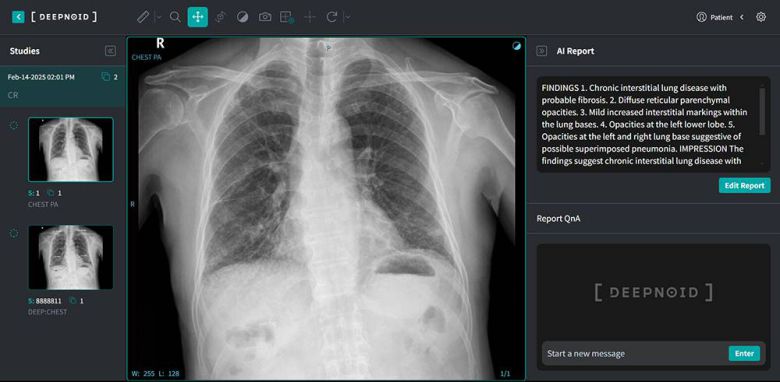

“M4CXR, 흉부 엑스레이를 AI 인색해 초안 생성하는 설루션”

인터뷰에 앞서 김태규 전무에게 딥노이드의 설루션 전반에 대한 소개를 부탁했다. 김태규 전무는 “M4CXR은 흉부 엑스레이 데이터로 판독 소견서 초안을 자동으로 생성하는 설루션이다. 기술 측면에서는 2015년부터 딥러닝 관련 연구를 시작했고, 자기 공명 혈관조영술(MRA) 결과를 기반으로 뇌동맥류를 검출하거나 다양한 병리 영상 등을 통해 대장암, 신장암, 위암 등의 질환도 분석해서 검출하는 기술 등을 개발해 왔다”라고 배경을 설명했다딥노이드의 흉부 엑스레이 데이터 분석 및 판독 소견서 생성 AI ‘M4CXR’, AI 판독 소견서 생성에 퓨리오사AI NPU가 도입될 예정이다 / 출처=딥노이드 |

이를 기반으로 AI 기반 흉부 X-Ray 진단보조 설루션 딥:체스트(DEEP:CHEST)를 개발하고 최근에는 M4CXR로 기능을 업그레이드 중이다. 아울러 AI 기반의 뇌 MRA용 딥 뉴로(DEEP:NEURO), 폐 질환 대응 딥 렁(DEEP:LUNG) 등의 의료 AI 서비스도 개발했다. 이중 딥 뉴로(DEEP:NEURO)는 혁신의료기기로 선정돼 비급여로도 수가가 지급되는 게 특징이다. 산업용 엑스레이를 위한 스카이마루:시큐리티(Skymaru:security), 딥시큐리티(DEEP:Security), 딥팩토리(DEEP:Factory) 등의 설루션도 있다.